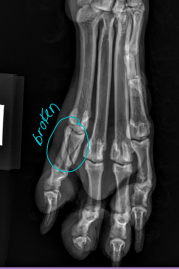

Digits & Metacarpal/Metatarsal Bones

Check each digit/nail bed and webbing

Pain, abnormal size, foreign material, draining tracts

Flex/extend phalangeal joints

Carpal, Metacarpal, Digital, Metatarsal Fractures

Very common, greyhounds

Tx: closed reduction + caudal splint (Rx #1), IM pins/plates + caudal splint (Sx)

Sx indicated if open, grossly displaced, intra-articular, or all 4 fractured

Digital: caudal splint bandage for 6w